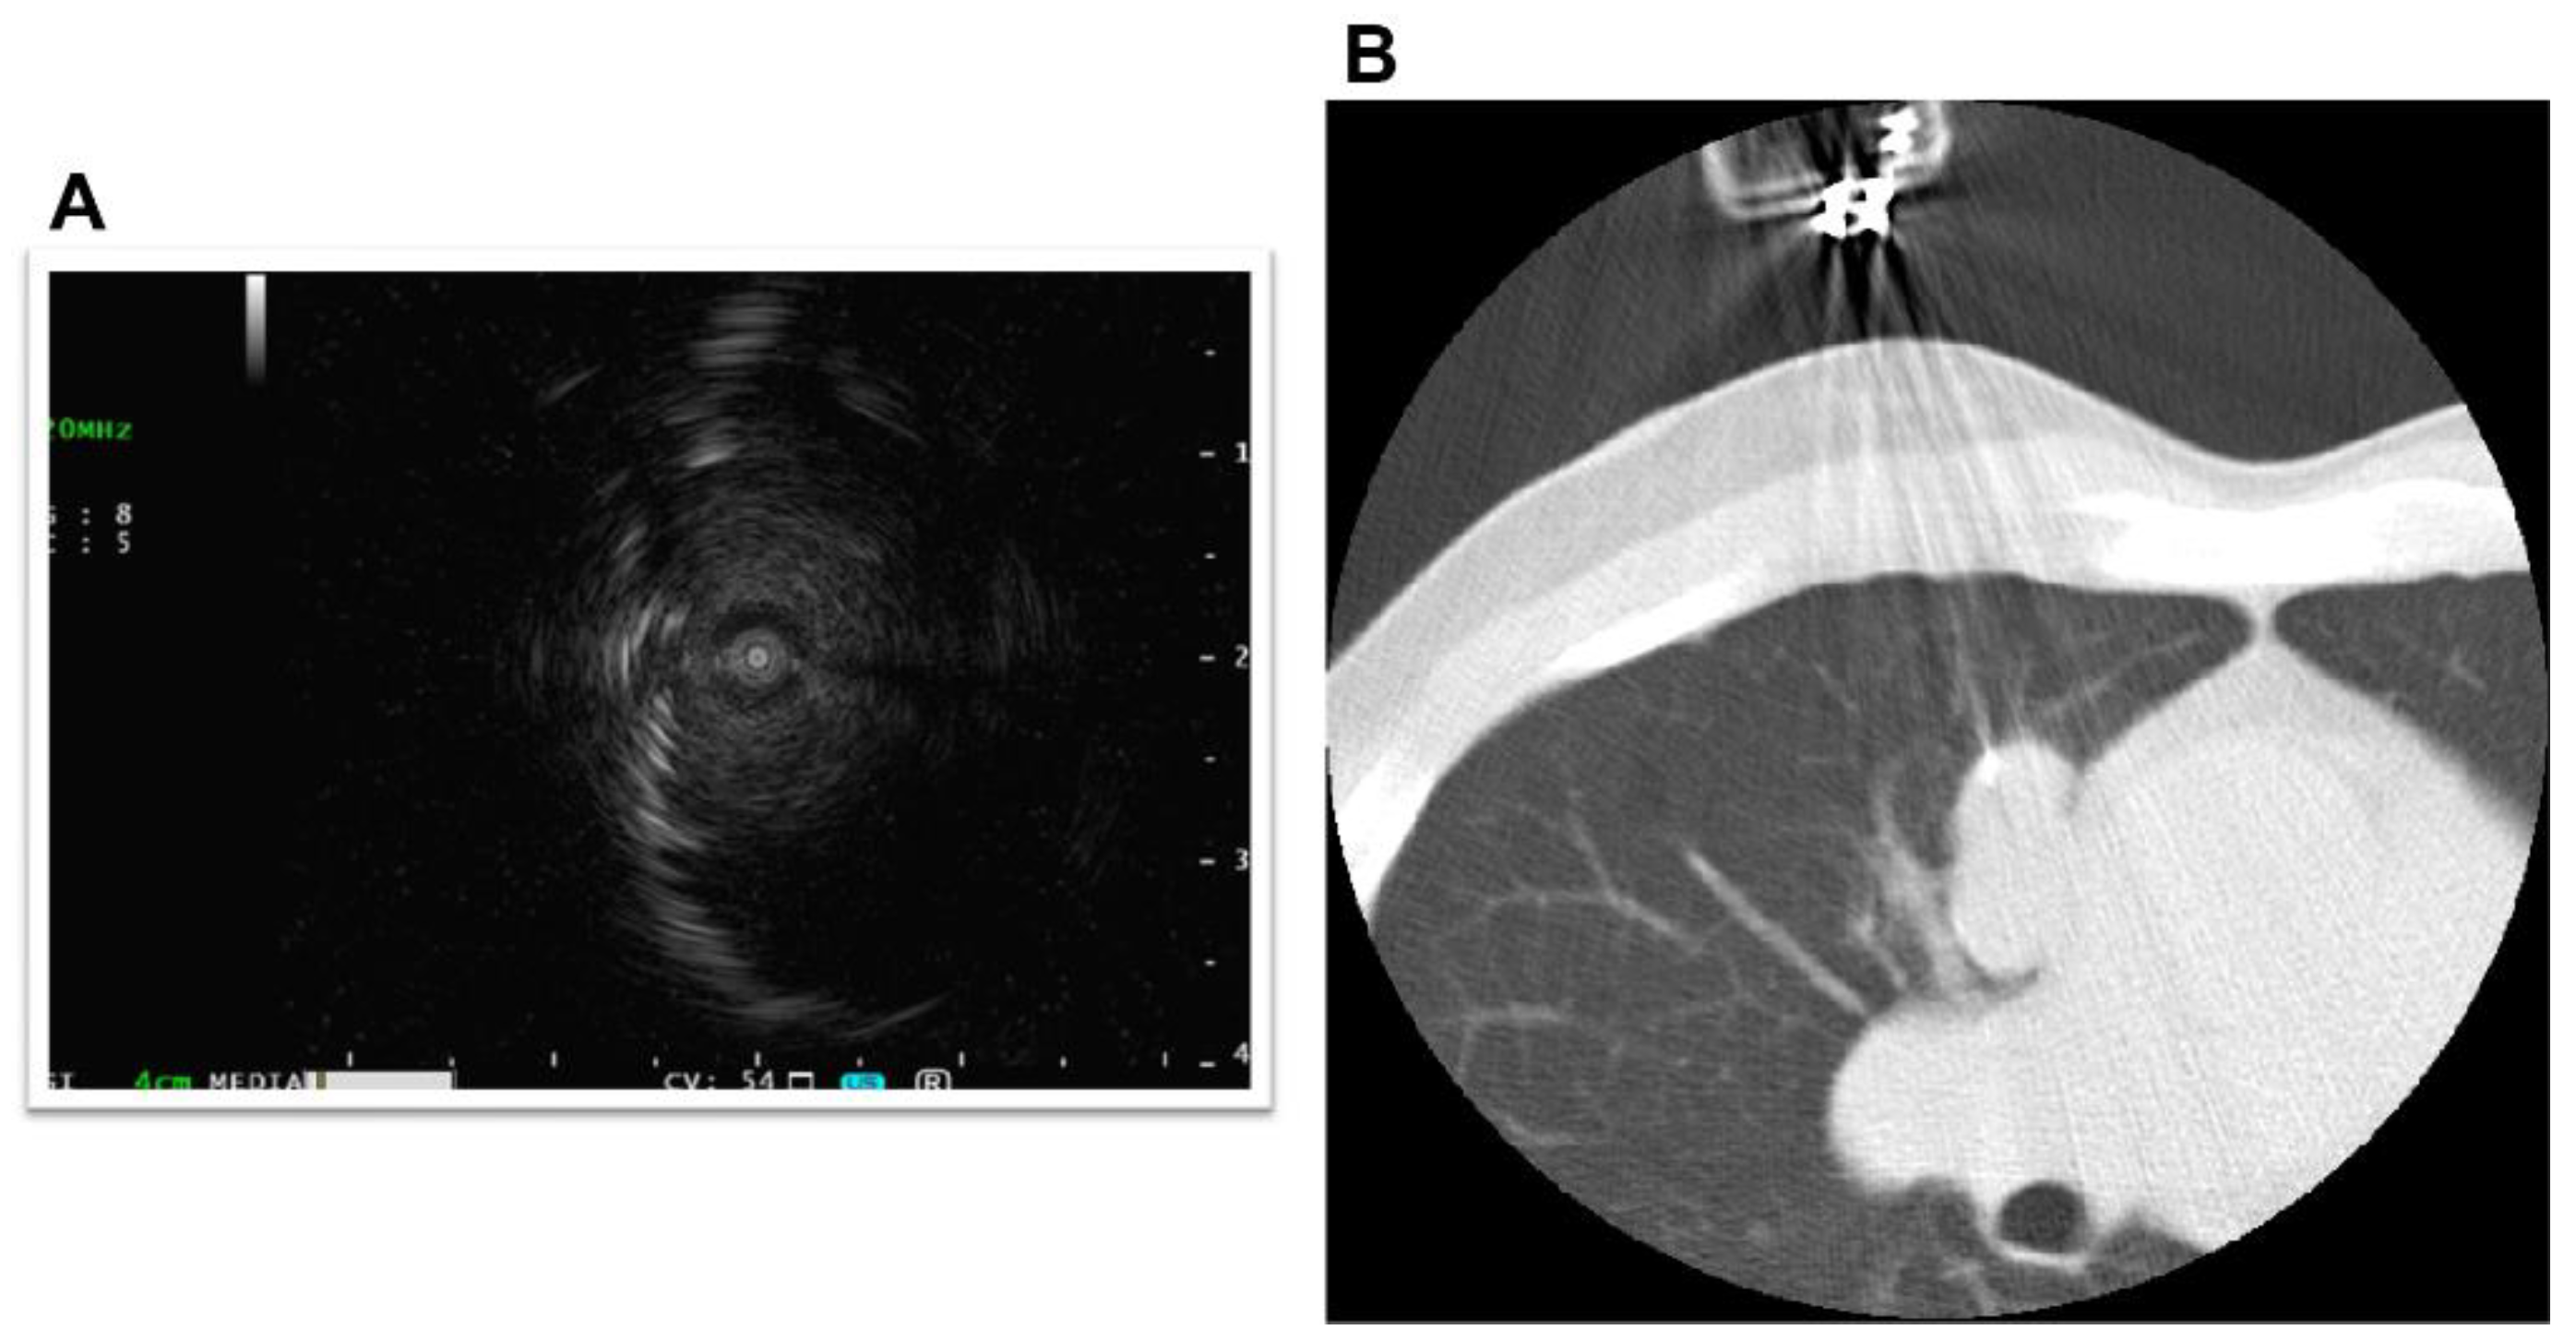

The primary lesion was located between the mediastinum and the right lung lobe, thus, it was difficult to distinguish whether the tumor originated from the mediastinum or the lungs. A thin bronchoscope with endobronchial ultrasonography and a guide sheath was inserted into the right B3biαx bronchial branch, and a biopsy within the tumor was performed. However, the histopathological study showed no diagnostic findings. CT-guided needle biopsy (CTNB) was then performed (Figure 2A,B). An expert pathologist revised the tissue specimen sampled by CTNB. The pathology report revealed a solid tumor with malignant squamous cells and scarring tissue and positive immunostaining for p40 and CK5/6. The pathological diagnosis was non-keratinized squamous cell carcinoma (Figure 3A–D). The differential diagnosis between thymic carcinoma and primary lung cancer was difficult based on imaging and histopathological findings. A PET/CT scan showed a primary tumor with high 18F-fluorodeoxyglucose accumulation, a maximum standardized uptake value of 10.95, and multiple nodules with a maximum standardized uptake value of 7.08 in the right lung interlobar region and pleura. The diagnosis was cancerous pleural dissemination (Figure 4A–F). The tumor was negative for epidermal growth factor receptor (EGFR) gene mutation, anaplastic lymphoma kinase (ALK) fusion gene, and the proto-oncogene tyrosine-protein kinase (ROS1). The degree of tumor PD-L1 (22C3) staining was low (5–10%). The tumor was considered unresectable.

Figure 2.

Bronchoscopy and computed tomography-guided biopsy. A thin bronchoscope, endobronchial ultrasonography, and a guide sheath were used during the bronchoscopy (A). Biopsy was performed under computed tomography guidance (B).